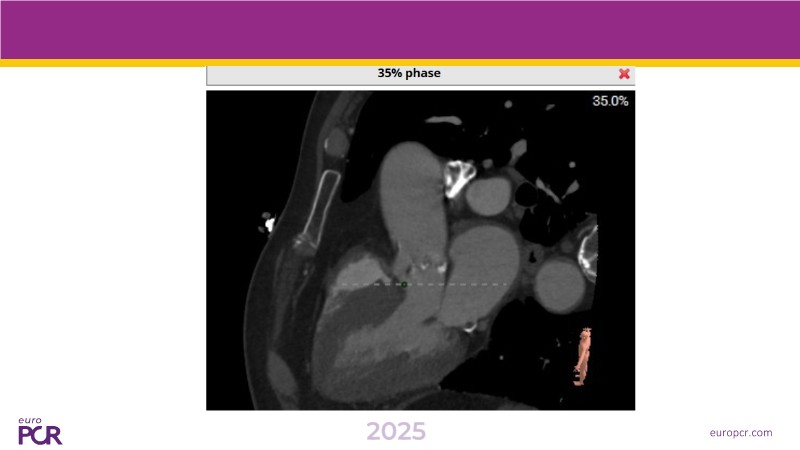

This session presents the latest updates on the novel Myval Octapro transcatheter heart valve (THV), based on one year of real-world clinical experience. Experts share practical tips and clinical cases that highlight how this innovative device can improve TAVI patient outcomes. The session also addresses imaging and sizing strategies critical for TAVI planning, as well as procedural best practices for successful implantation of the Myval Octapro THV.

- To learn from the experts best-in-the-class TAVI practice: pre-procedural (imaging, sizing rationale, treatment strategy), procedural tips and tricks and post-procedural management